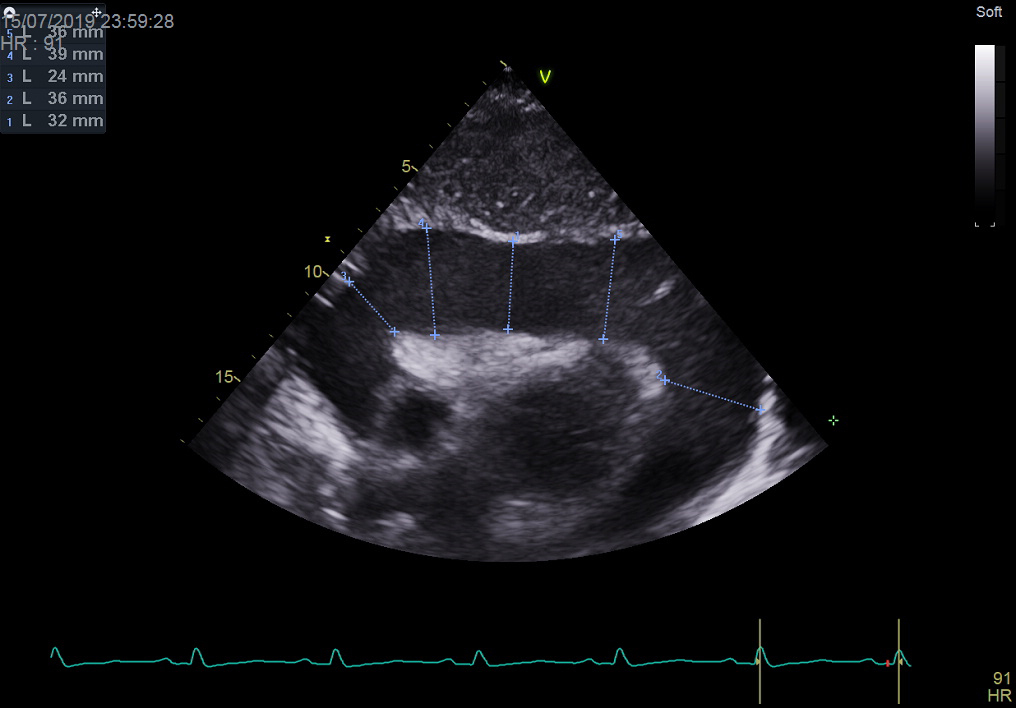

L’échographie cardiaque donnera le diagnostic.

– la tamponnade liquidienne (l’échographie cardiaque donnera le diagnostic) ;